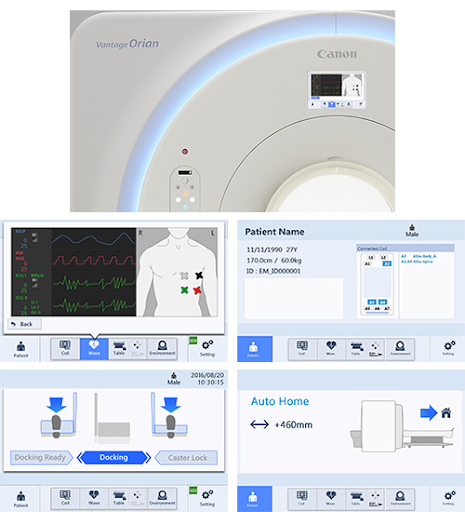

Удобный в управлении

Интерфейс гентри переработан и отображает важную информацию о пациенте, чтобы оптимизировать рабочий процесс и сэкономить время настройки прибора.

На дисплеях демонстрируются все этапы обследования.